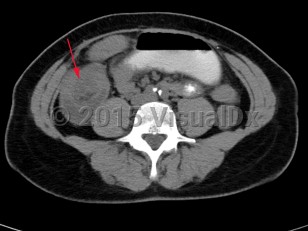

Intussusception is a telescoping or invagination of a part of the intestine into the lumen of an adjacent segment. Intussusception can present with variable severity. It can present with bowel ischemia and perforation with need for emergent surgical intervention, or it can present as relaxing / remitting abdominal pain of unclear etiology with intermittent symptoms and no signs of systemic illness. Jejunojejunal, jejunoileal, ileoileal, ileocolonic, and colocolonic are all types of intussusception that can occur, with the majority involving the small intestine.

Intussusception occurs in children and adults. It is the most common cause of bowel obstruction in children, where it presents with sudden onset of acute abdominal pain and inconsolability, and at times with emesis, a palpable abdominal mass, or hematochezia. Tucking knees into the torso is consoling in some instances. In pediatrics, intussusception is most commonly due to viral illnesses, with mesenteric lymphadenopathy creating a lead point to trigger intussusception. Tumors, polyps, Meckel diverticulum, or postsurgical adhesions are additional causes that can trigger intussusception.

Initial management requires ensuring hemodynamic stability, as many patients are dehydrated, and assessing concern for bowel perforation, which could require broad-spectrum antibiotics and urgent surgical intervention. Air or barium enemas can be both diagnostic and therapeutic. However, intussusception will frequently recur, in which case surgical resection is often required. Further imaging (ie, small bowel x-ray series, CT or MRI abdomen) can be utilized to identify the etiology if it is unknown based on presenting symptoms and a barium / air enema.